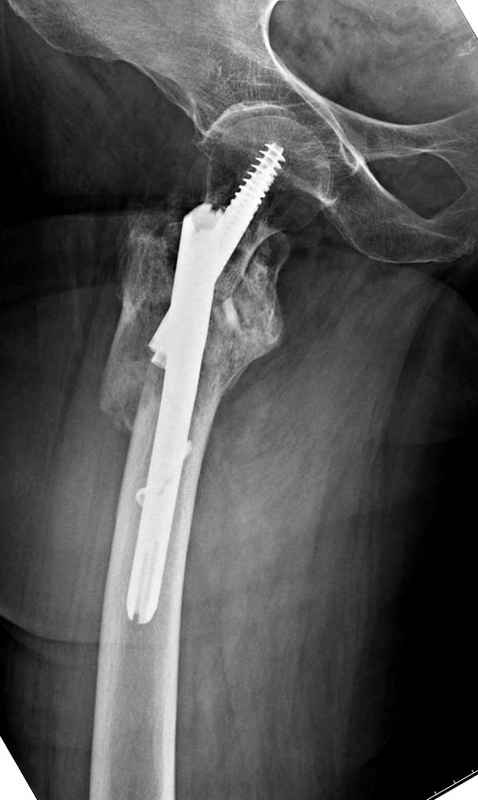

[Ortho] Чрезвертельный перелом бедра

Здесь 83 года, травма в результате падения

Имя     : Hip final.jpg